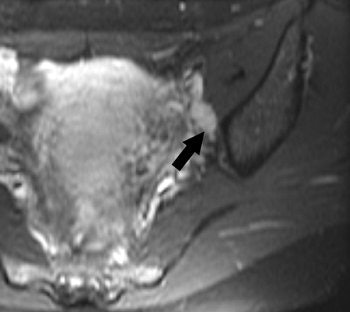

| Transverse T2-weighted MR images in 35-year-old patient with cervical carcinoma obtained with, above, standard sequence (2705/80; imaging time, 4 minutes 3 seconds) and, below, fast sequence (4933/100; imaging time, 39 seconds). Motion artifacts (arrowhead) are absent in image below and moderate in image above; thus, delineation of intact cervical stroma is even better with the fast sequence. Detection of ascites (arrow) is better (in image below). The remaining tissue contrasts and visual SNRs in the two images are comparable. |

According to the results, 27 solid tumors were diagnosed in 24 patients and 12 cystic tumors, or liquid-containing disorders, were found in 10. The visual SNR for the fast sequence was comparable to the standard one in all 33 patients. The tissue contrast between solid tumors and muscle also was comparable. With the fast sequence, there was significantly higher contrast between urine and muscle, between ovarian cysts and ovarian stroma, and between cystic tumors or liquids and muscle.

Motion artifacts were significantly reduced with the fast sequence, and the final MRI diagnosis did not differ between the two sequences. On the downside, the tissue contrast of the zonal anatomy could not be analyzed in 33% of the women.

Most importantly, the imaging time for the fast sequence was 39 seconds versus four minutes and three seconds with the standard sequence.